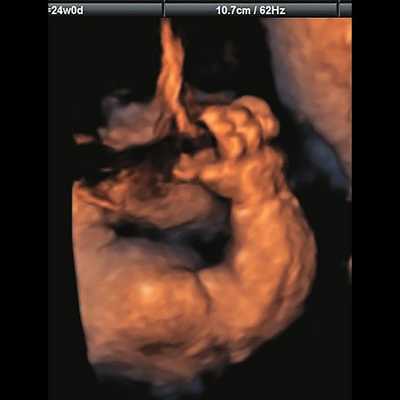

д) Объемная реконструкция. Видны правильно установленные пальцы.

б) Объемная реконструкция. Видны высокий выпуклый лоб, расширенный передний родничок и сагиттальный шов, правильная установка пальцев.

Основные ультразвуковые характеристики плодов, полученные при нашем исследовании, отображены в таблице 1 и на рис. 1-4.

| Срок беременности | Голова | Грудная клетка | Конечности | Дополнительные находки |

|---|---|---|---|---|

| Набл. 1. 24,3 нед. | БПР - 25,3 нед. ОГ - 24,6 нед. Аномально повышенная бороздчатость и выпуклость извилин нижнемедиальной поверхности височных долей (рис. 1а). | Торакоабдоминальное соотношение - 66,7% (рис. 1б) Длина ребра - среднее для 16 нед. | Бедренная кость 19,6 мм (47,8% от должной), изогнута ("телефонная трубка") (рис. 1в). Остальные кости - среднее для 15 нед. | Уплощенные тела поясничных позвонков. |

| Набл. 2. 20,3 нед. | БПР - 21,5 нед. ОГ - 20,3 нед. Уплощенный затылок. Выпуклые темпоральные бугры (рис. 2а). Аномально повышенная бороздчатость и выпуклость извилин нижнемедиальной поверхности височных долей (рис. 2б). | Торакоабдоминальное соотношение - 63,3% (рис. 2в) Окружность груди - среднее для 18 нед. Длина ребра - среднее для 15 нед. | Бедренная кость 17,7% (61% от должной), изогнута ("телефонная трубка") (рис. 2г). Остальные кости - среднее для 13-14 нед. | Гипоплазия костей носа. |

| Набл. 3. 24 нед. | БПР - 30 нед. ОГ - 27,2 нед. Уплощенный затылок. Выпуклые темпоральные бугры (рис. 3а). Аномально повышенная бороздчатость и выпуклость извилин нижнемедиальной поверхности височных долей (рис. 3б). | Торакоабдоминальное соотношение - 56,6% (рис. 3в) Окружность груди - среднее для 20 нед. Сердце/грудь (см 2 ) - индекс 0,6. | Бедренная кость 23,1 мм (57% от должной), изогнута ("телефонная трубка") (рис. 3г) Остальные кости - 50% для 15-16 нед. Нормальная установка пальцев кисти (рис. 3д). | Многоводие. |

| Набл. 4. 26,5 нед? | БПР - 22,6 нед. ОГ - 22,6 нед. Форма - трилистник (рис. 4а). Боковые желудочки - 22 мм, высокий лоб, расширенный родничок, сагиттальный шов (рис. 4б). | Торакоабдоминальное соотношение - 65,7% (рис. 4в). Окружность груди - среднее для 23 нед. Колоколообразная форма. | ДБ - 23 мм (51% от должной). Остальные кости - 50% для 15-17 нед. Нормальная установка пальцев кисти (рис. 4б). | Уплощенные тела поясничных позвонков (рис. 4г). |

Примечание. БПР - бипариетальный размер, ОГ - окружность головы, ДБ - длина бедренной кости.

Длину бедренной кости оценивали по региональным нормативам, а остальные кости - по Ph. Jeanty. Окружность грудной клетки оценивали по U. Chitkara и соавт. [14], длину ребер - по A.Z. Abuhamad [15].

В наблюдениях 1-3 наличие изогнутой бедренной кости (по типу "телефонной трубки") (рис. 1в, 2г, 3г) позволяло предположить наличие ТД I типа. Целе направ ленное исследование головного мозга этих плодов в дополнение к описанным скелетным признакам показало и картину ДВД. Была выявлена аномально повышенная бороздчатость и выпуклость извилин нижнемедиальной поверхности височных долей у плодов в наблюдениях 1-3 (рис. 1а, 2б, 3б). Это позволило установить диагноз ТД I типа.

Наиболее важным, с точки зрения A.M. Bircher и соавт. [16], является необходимость дифференцировки ТД с ахондроплазией, так как последняя является частой и совместимой с жизнью скелетной дисплазией. При этом наиболее эффективным дифференциальным признаком предлагается степень укорочения бедренной кости: невыраженное укорочение (ДБ составляет до 80% от должной) характерно для ахондроплазии, тогда как при ТД укорочение выраженное (ДБ составляет 30-60%). В наших наблюдениях укорочение ДБ составляло 47-61% от должной. В работе A. Khalil и соавт. [17] показано увеличение диафизарно-метафизарного угла (более 130°) бедренной кости при ахондроплазии. С нашей точки зрения, в дифференциальной диагностике ТД с гомозиготной формой ахондроплазии решающую роль может играть семейный анамнез, а с гетерозигототной - наличие узкой грудной клетки. Кроме того, как видно по нашим наблюдениям, при ТД определяется правильная установка пальцев кисти (рис. 3д, 4б) в отличие от ахондроплазии, при которой определяется установка пальцев в виде "трезубца".